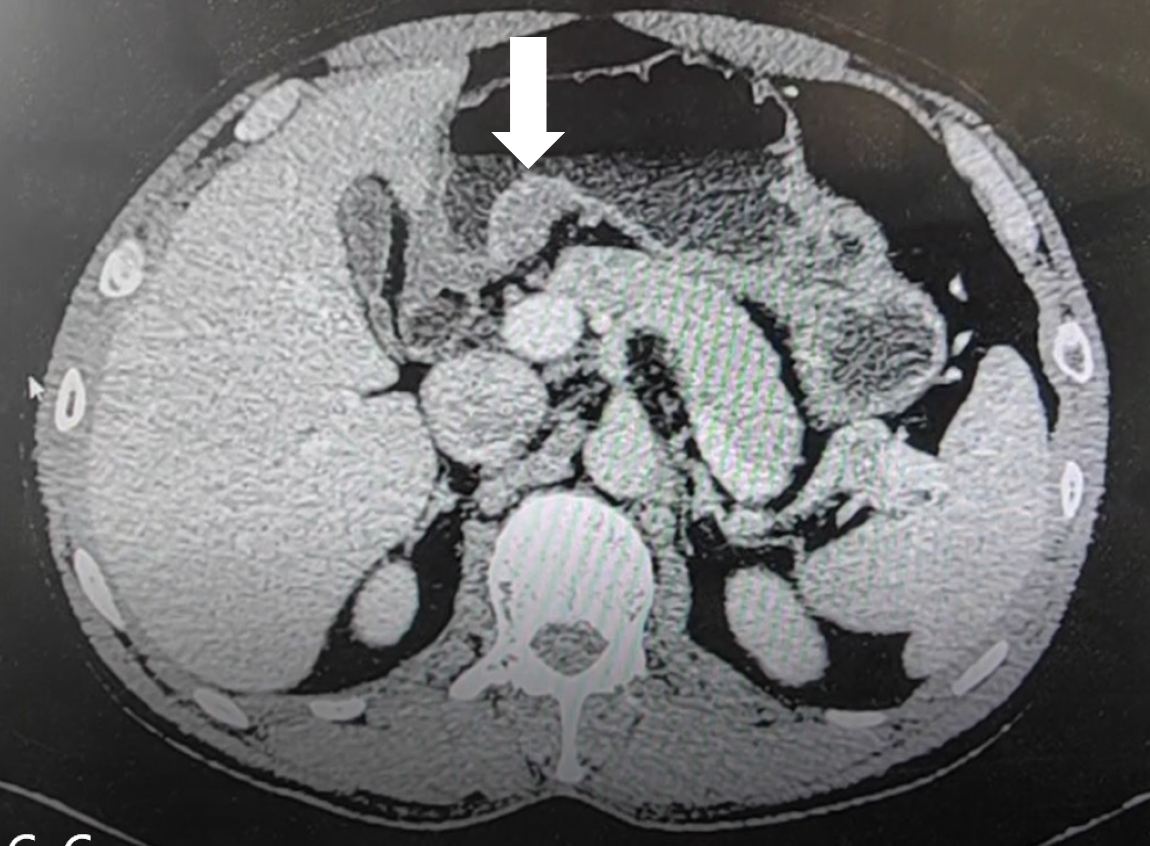

Figure 3 Gastric-enhanced computed tomography scan.

Gastric-enhanced computed tomography scan shows a soft tissue mass located beneath the mucosa on the small-curvature side of the antrum (white arrow).